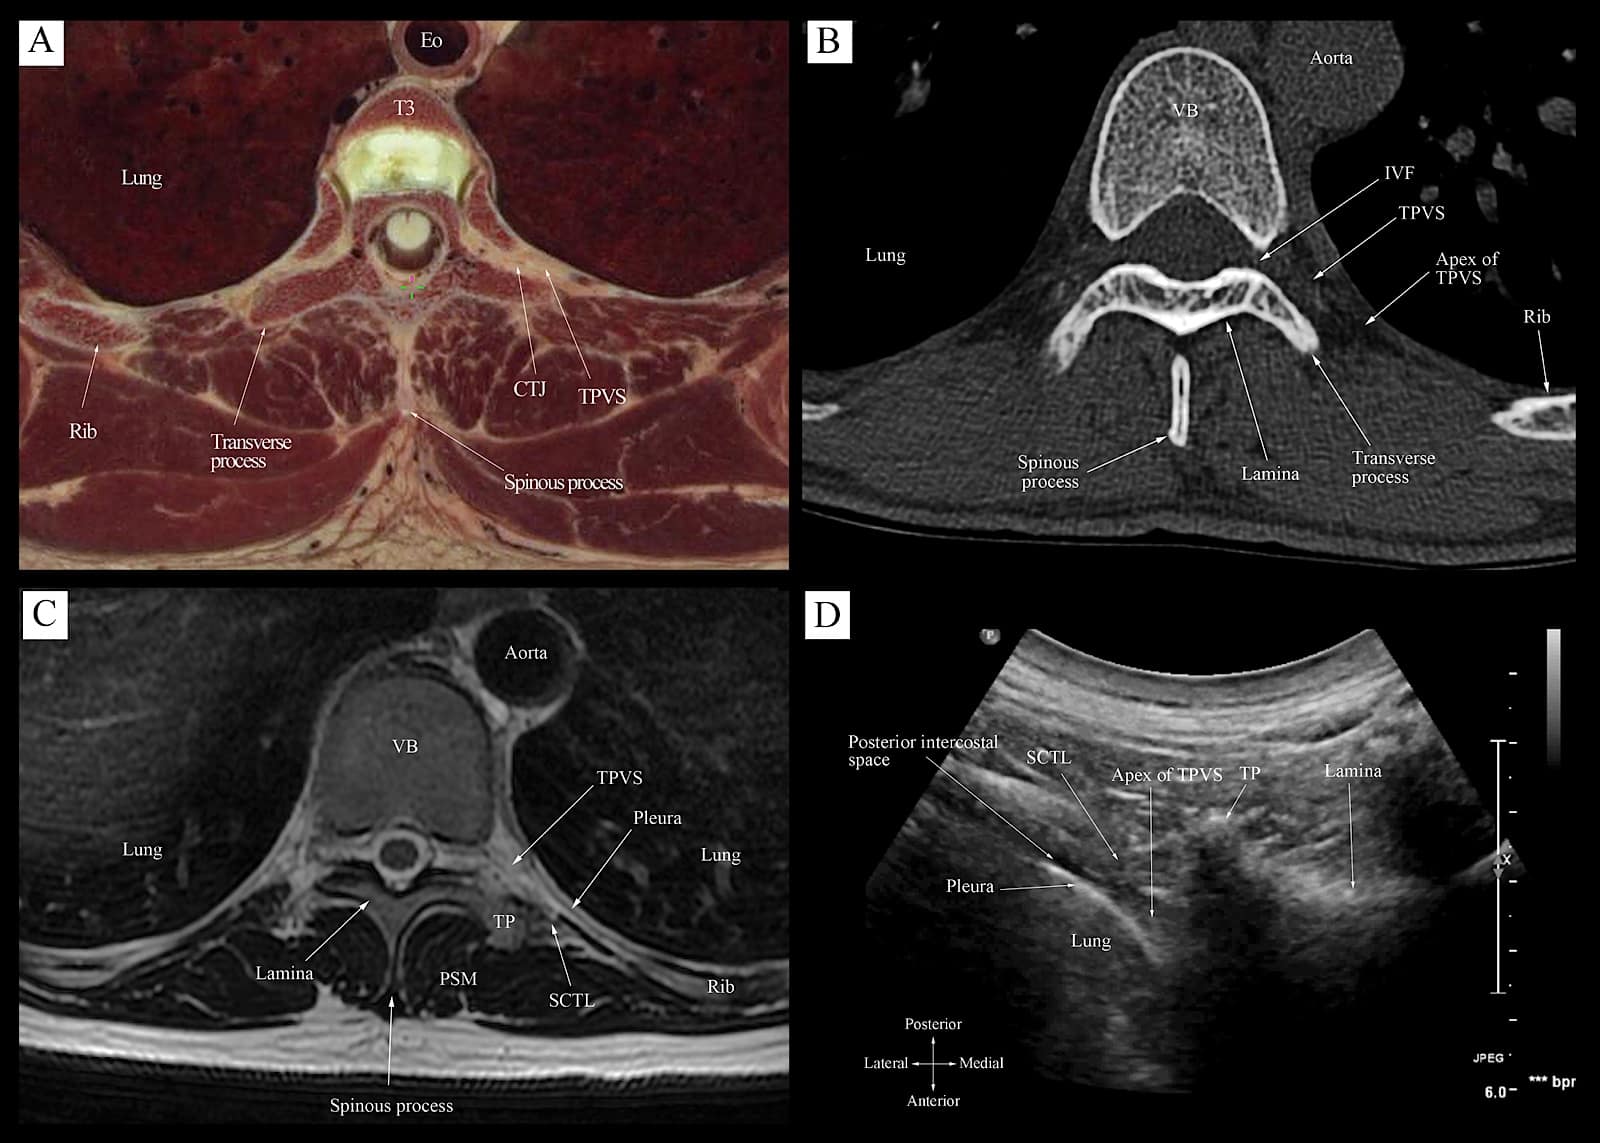

The Transverse Ultrasound Scan Sequence

The target transverse ultrasound window at the level of the IAP is obtained through three sequential steps, over three contiguous osseous anatomical landmarks (Figure 10), at the target vertebral level.11,62,63 The sequential steps are as follows: Step 1 at the transverse process-rib complex level (Figure 10, red box). Step 2 at the transverse process level (Figure 10, blue box), and step 3 at the IAP level (Figure 10, green box). Based on the underlying osseous and musculoskeletal structures, these three ultrasound scan windows produce three distinct sonograms (Figure 9). Correlative cadaver anatomic-CT-MRI and transverse sonograms for steps 2 and 3 of the transverse scan sequence are presented in Figures 11 and 12.

Figure 11. Correlative transverse cadaver anatomic (Fig 11A), CT (Fig 11B), MRI (T1 weighted, Fig 11C), and ultrasound (Fig 12D) images of the thoracic paravertebral region from the level of the vertebral body and transverse process corresponding to the level at which the transverse scan is performed (position 2, Fig 10).

Eo = esophagus, CTJ = costotransverse junction, TPVS = thoracic paravertebral space, VB = vertebral body, PSM = paraspinal muscle, IVF= intervertebral foramen, TP = transverse process, SCTL = superior costotransverse ligament

Reproduced with permission from the Department of Anesthesia and Intensive Care, The Chinese University of Hong Kong, Faculty of Medicine, www.aic.cuhk.edu.hk/usgraweb.